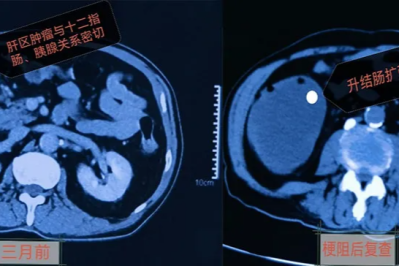

河北一洲肿瘤医院外科成功救治一名高龄双原发结肠癌合并急性肠梗阻患者